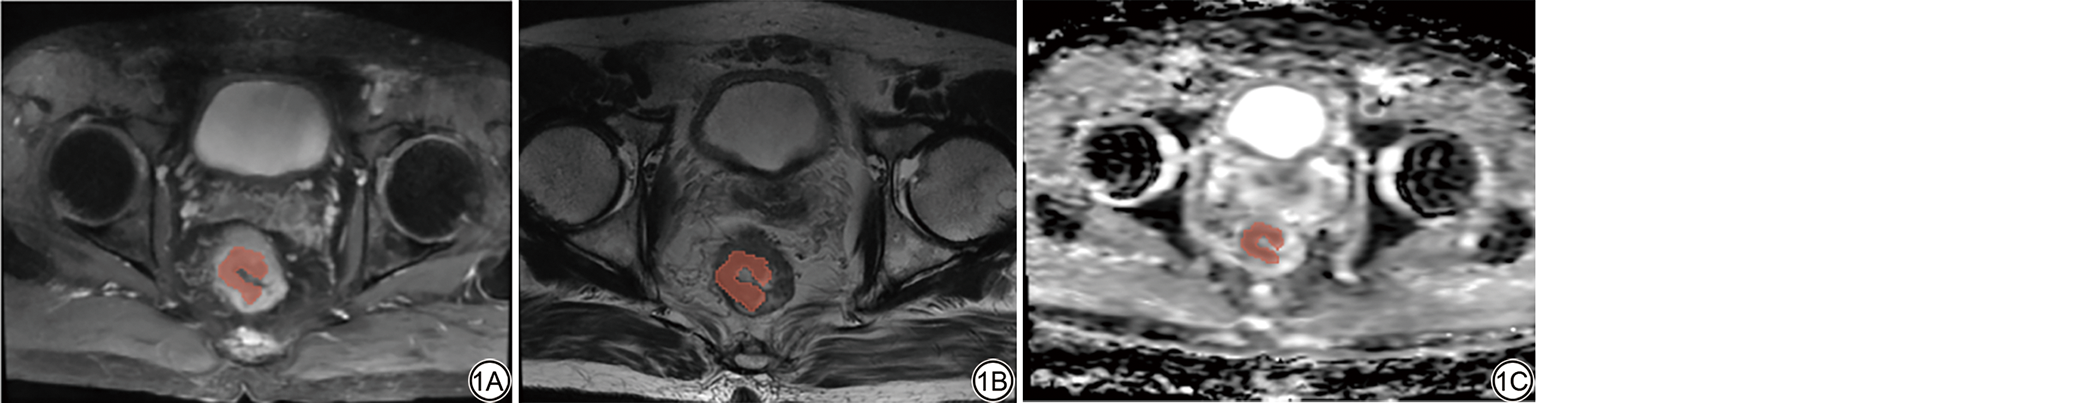

为了确保DCE-T1WI图像分辨率和体素大小的统一性,首先使用线性插值对其进行重新采样处理。随后,通过为绝对灰度离散化设置固定的bin大小,对灰度离散化进行归一化。将处理后的图像调入(syngo MMWP, VE40 A, Siemens AG)后处理工作站,应用Tissue4D由髂内动脉的时间-信号强度曲线(time-intensity curve, TIC)确定血流峰值期,由上述两位放射科医师在该期勾画灌注最高区域作为ROI,随后系统自动生成(图3图4)灌注图像和灌注参数值[18],其包括灌注参数对比剂增强比率(contrast enhancement ratio, CER)、钆对比剂浓度-时间曲线下初始面积(initial area under the gadolinium concentration-time curve, IAUCG)、最大斜率(Maxslope)、容积转运常数(volume transferconstant, Ktrans)、回流速率常数(rate constant, Kep)、细胞外血管外间隙容积分数(extracellular extravascular volume fraction, Ve)的数值。为了评估其测量结果的一致性和可靠性,上述两位放射科医师随机选取了30名患者,并在4周后重新测量这些参数,并保留ICC>0.75的灌注参数(表1)。然后取两组DCE-MRI灌注参数的平均值用于进一步分析。

图4  DCE灌注图的ROI示意图。图中圈画的彩色区域分别是MSI状态DCE-MRI灌注图中的ROI(4A)、MSS状态DCE-MRI灌注图中的ROI(4B)。DCE:动态对比增强;ROI:感兴趣区;MSI:微卫星不稳定;MSS:微卫星稳定。

Fig. 4  The ROI delineation diagram of DCE perfusion parameters. The colored regions marked in the figure represent the ROI in the DCE-MRI perfusion images for the MSI state (4A) and the ROI in the DCE-MRI perfusion images for the MSS state (4B). ROI: region of interest; DCE: dynamic contrast-enhanced; MSI: microsatellite instability; MSS: microsatellite stability.